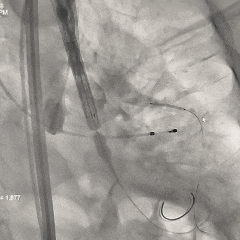

20mm球囊预扩

无腰无漏,右冠显影正常;RN侧钙化融合推挤球囊贴靠左窦侧,可见左冠显影欠佳,考虑有球囊贴靠STJ的原因,决定预埋支架保护再准备瓣膜释放